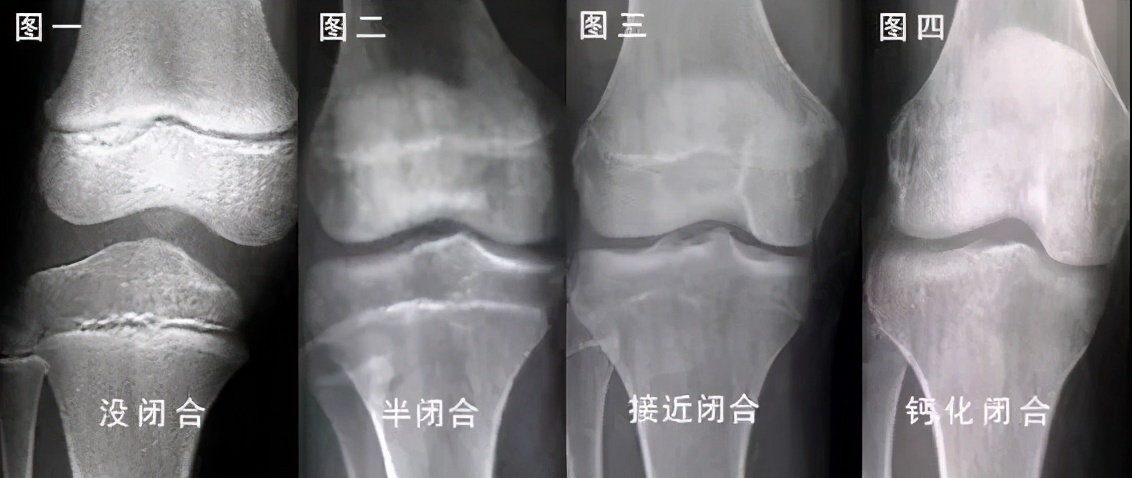

骨骺线钙化

因为骨骼线一般在14,5岁的时候就开始闭合,之后逐渐钙化.

随着年龄的不断增长,骨骺线逐渐的钙化,当它完全钙化之后,人体就没有

随着年龄的增长,骨骺线会逐渐钙化.

在骨骺线闭合之前,骺软骨不断分裂增殖生成新的软骨,然后软骨变成骨